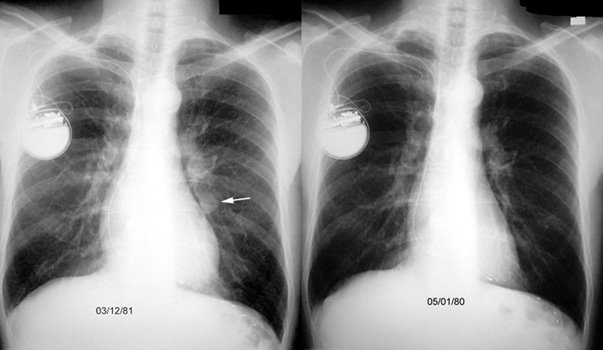

Первоначально врач проводит анализ жалоб пациента и сбор анамнеза. Далее для постановки диагноза проводят следующие исследования:

- рентгенологическое исследование грудной клетки;

- МРТ, КТ;